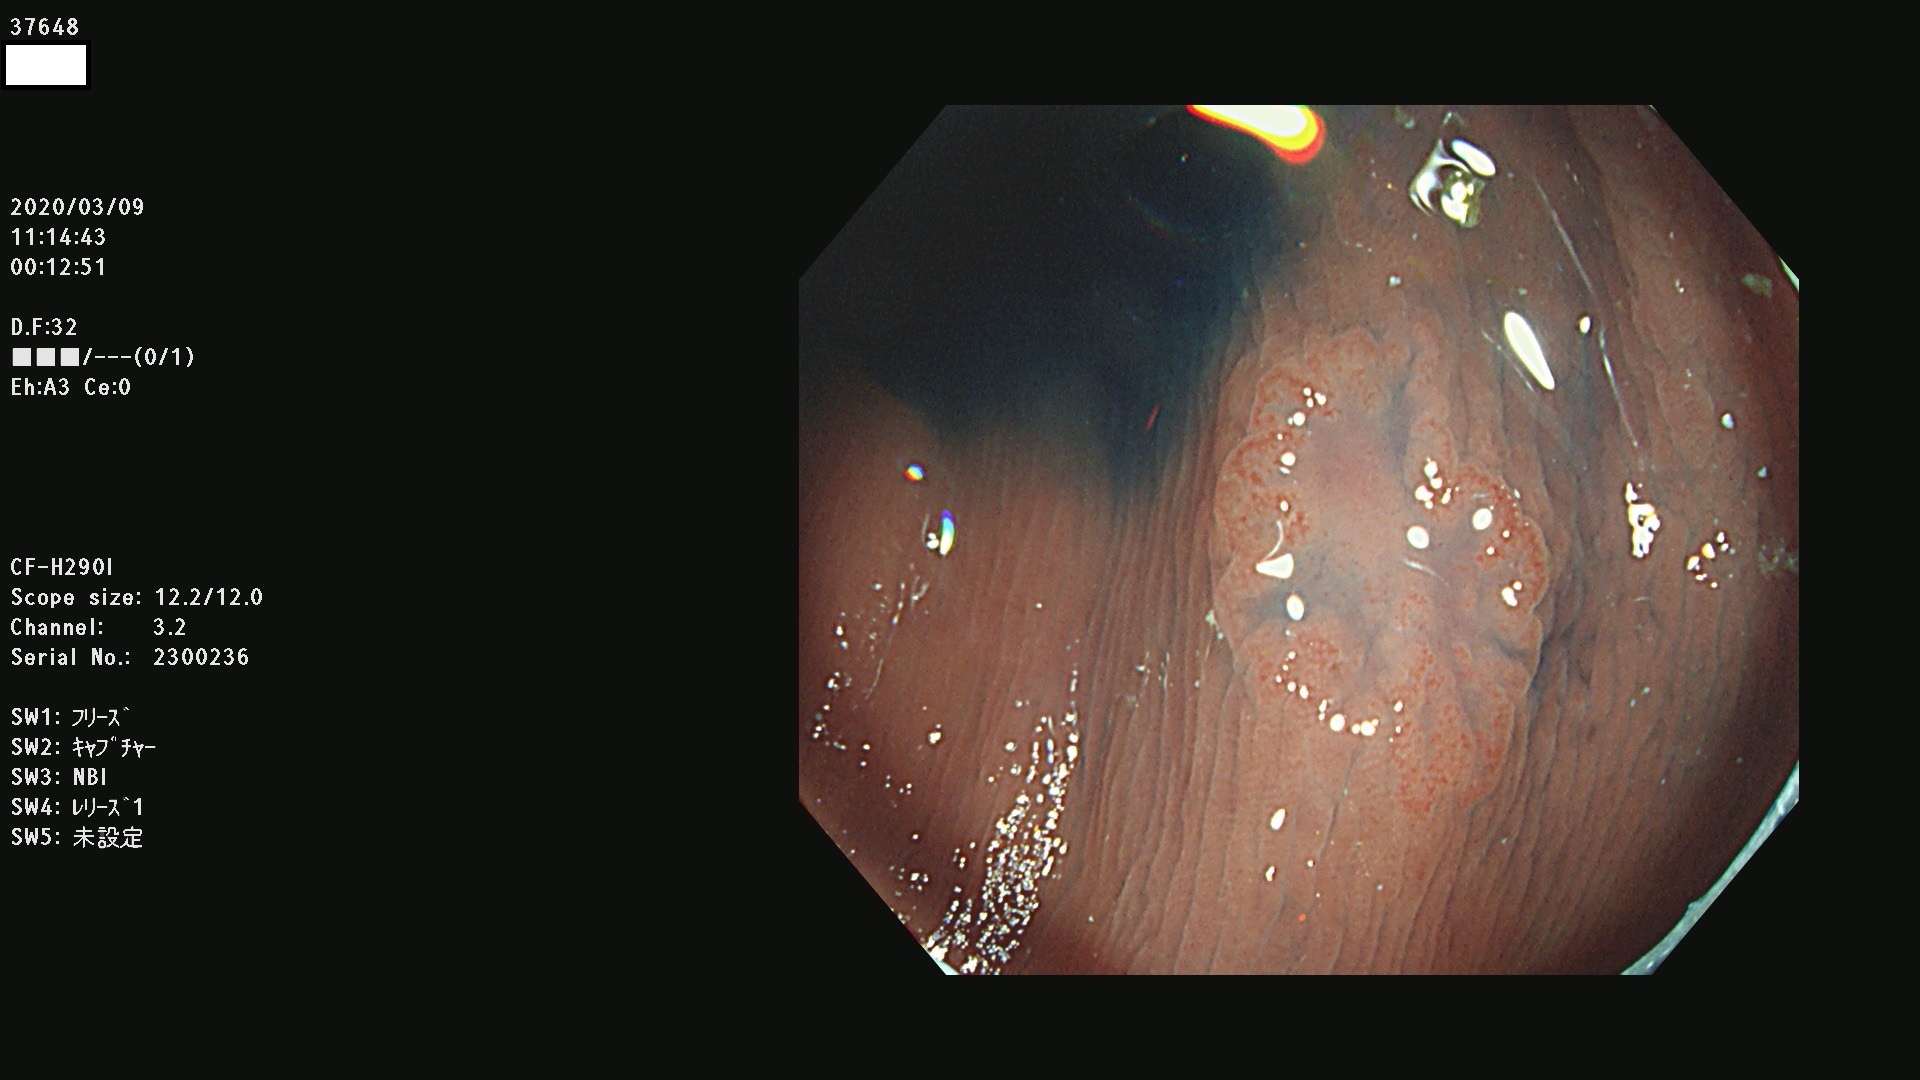

発見困難で危険性の高い平坦型病変(上記100名より抽出)